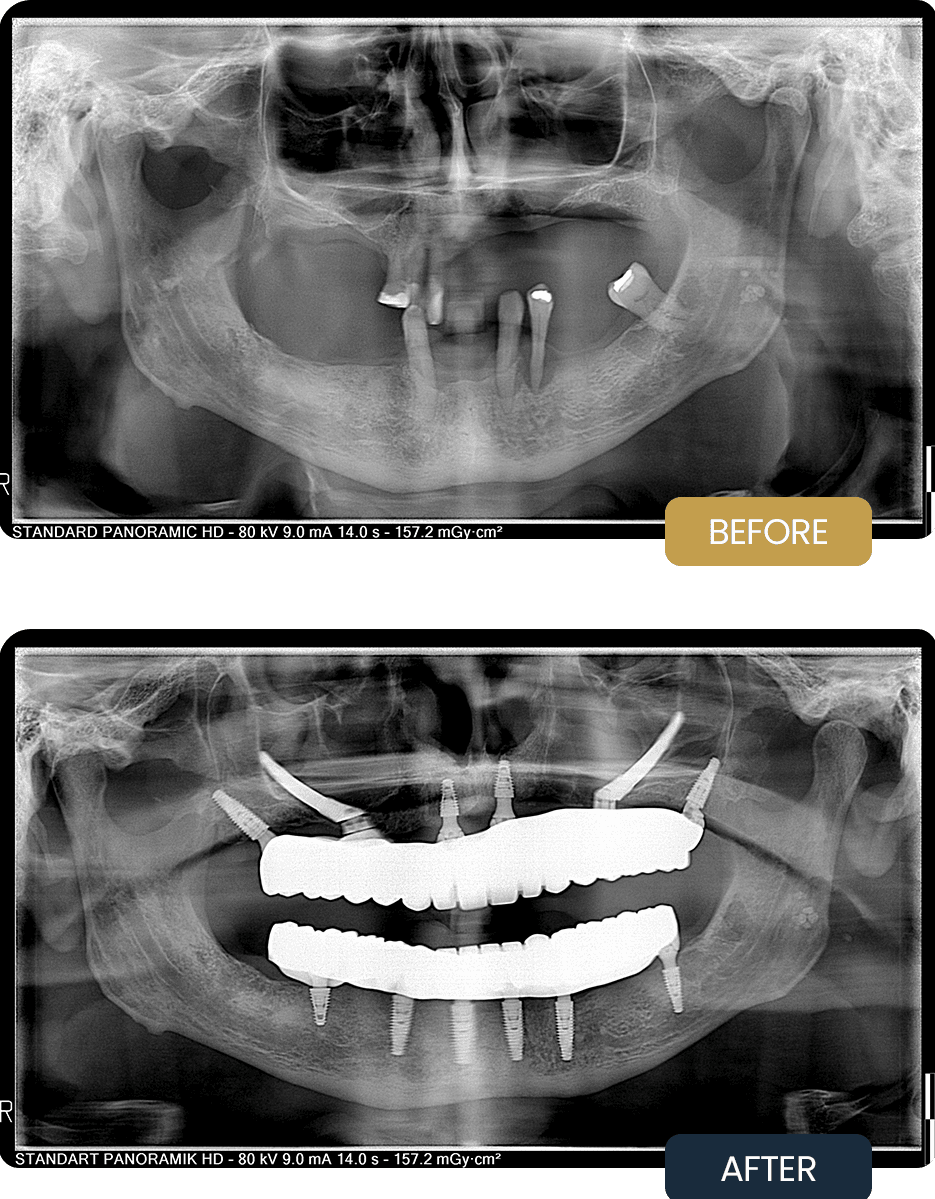

BEFORE

At initial presentation, Peter showed severe bone loss in the upper jaw, limiting the feasibility of conventional implant placement alone. Functional instability and reduced chewing efficiency were present in both jaws.

The pre treatment panoramic radiograph demonstrates the extent of bone deficiency in the upper jaw and the need for an advanced implant solution incorporating zygomatic support, along with comprehensive lower jaw rehabilitation.

AFTER

Post treatment panoramic imaging confirmed successful integration of all implants, including stable positioning of the zygomatic implants in the upper jaw and well aligned All on 6 implants in the lower jaw. Bone grafted areas and membrane supported sites showed appropriate healing conditions.

The final fixed prostheses restored strong chewing function, improved comfort, and long term stability, providing a reliable solution tailored to complex anatomical requirements and designed for predictable long term performance.